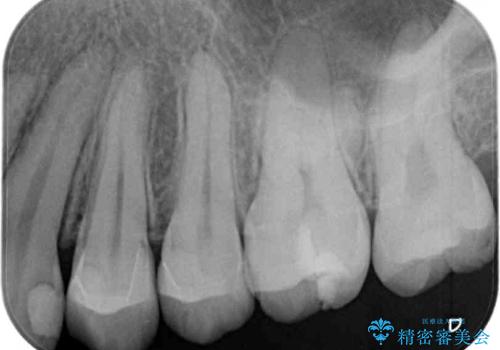

矯正治療後には、目立つ銀歯と隣接するむし歯をセラミックインレーにて修復治療することとしました。